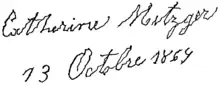

Beyond the cardinal four, other motor deficits, termed secondary motor symptoms, commonly occur.[27] Notably, gait disturbances result in the Parkinsonian gait, which includes shuffling and paroxysmal deficits, where a normal gait is interrupted by rapid footsteps—known as festination—or sudden stops, impairing balance and causing falls.[28][29] Most PD patients experience speech problems, including stuttering, hypophonic, "soft" speech, slurring, and festinating speech (rapid and poorly intelligible).[30] Handwriting is commonly altered in Parkinson's, decreasing in size—known as micrographia—and becoming jagged and sharply fluctuating.[31] Grip and dexterity are also impaired.[32]

In 1817, English physician James Parkinson published the first full medical description of the disease as a neurological syndrome in his monograph An Essay on the Shaking Palsy.[244][245] He presented six clinical cases, including three he had observed on the streets near Hoxton Square in London.[246] Parkinson described three cardinal symptoms: tremor, postural instability and "paralysis" (undistinguished from rigidity or bradykinesia), and speculated that the disease was caused by trauma to the spinal cord.[247][248]

There was little discussion or investigation of the "shaking palsy" until 1861, when Frenchman Jean-Martin Charcot—regarded as the father of neurology—began expanding Parkinson's description, adding bradykinesia as one of the four cardinal symptoms.[247][246][248] In 1877, Charcot renamed the disease after Parkinson, as not all patients displayed the tremor suggested by "shaking palsy".[246][248] Subsequent neurologists who made early advances to the understanding of Parkinson's include Armand Trousseau, William Gowers, Samuel Kinnier Wilson, and Wilhelm Erb.[249]